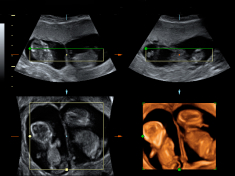

A lo largo del embarazo, el médico te recomendará una serie de pruebas diagnósticas para asegurarse que tu hijo se desarrolla correctamente, como la ecografía. Otras solo se prescriben cuando el ginecólogo sospecha que algo puede ir mal y necesita más datos para corraborarlo, como la amniocentesis o el control del bienestar fetal. Te contamos cómo y cuándo se realizan.